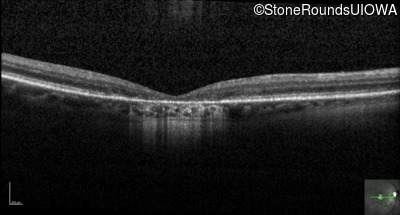

Optical Coherence Tomography - Right - 10/125

Exemplar / OCT Stack